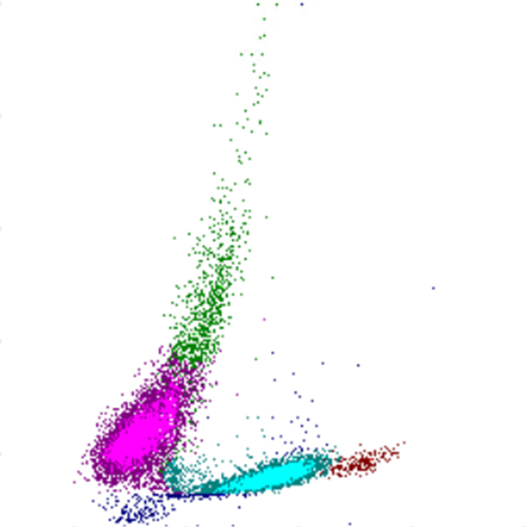

The white and red blood count of a pig is reminiscent of that of a patient with hemoglobinopathy and myelodysplasia. The substantial lymphocytosis of

9.5⋅109/L

is reminiscent of a chronic lymphatic malignancy.XN Scatterplots

SFL

SSC

Lymphocytes

Monocytes

Neutrophils

Eosinophils

Basophils

Leukocytes

NRBCs

Debris

Erythrocytes

Reticulocytes

RBC fragments

Platelets

immature platelets

Granulocytes

The WDF channel shows a clear dominance of the lymphocytic population , probably involving misclassification of lymphocytes as monocytes . The population of neutrophilic granulocytes is flattened and shifted to the left, which may indicate hypogranulation and/or aberrant nuclear segmentation . Only reduced erythrocyte size is observed in the RET tract .